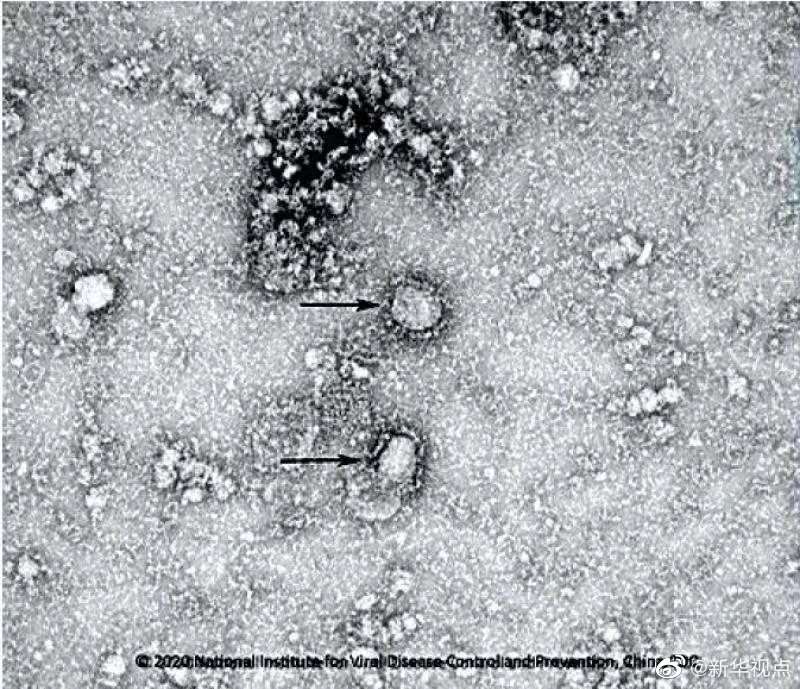

國(guó)家病原微生物資源庫(kù)于2020年1月24日發(fā)布了由中國(guó)疾病預(yù)防控制中心病毒病預(yù)防控制所成功分離的我國(guó)第一株病毒毒種信息及其電鏡照片、新型冠狀病毒核酸檢測(cè)引物和探針序列等國(guó)內(nèi)首次發(fā)布的重要權(quán)威信息,并提供共享服務(wù)。看病毒“真容”↓↓↓(記者田曉航、王秉陽(yáng))